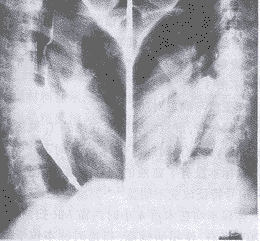

1.X線檢查X線檢查應在急性炎症消退後,病人能吞服流食方可作食管造影檢查。如疑有食管瘺或穿孔,造影劑可流入呼吸道,最好採用碘油造影。依據病變發展的不同階段及損傷程度不同,輕者:早期為食管下段繼發性痙攣,黏膜紋理尚正常,也可輕度增粗、扭曲、後期瘢痕、狹窄不明顯。中度:食管受累長度增加,繼發性痙攣顯著,黏膜紋理不規則呈鋸齒狀或串珠狀。重症者:管腔明顯縮小,甚至呈鼠尾狀。